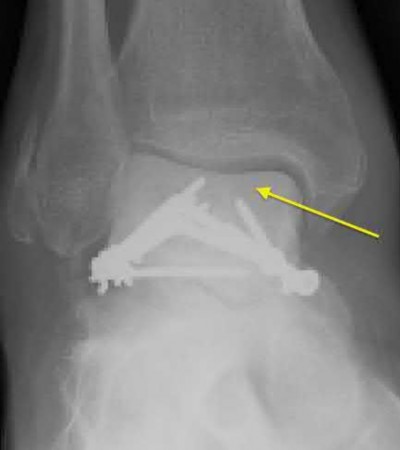

A 25-year-old male sustains an ankle fracture dislocation and undergoes open reduction and internal fixation. He returns to clinic five months following surgery complaining of continued ankle pain and instability with weight bearing. His immediate post-operative AP radiograph is seen in Figure A. Which of the following could have prevented this patient from developing persistent pain?

The patient presents with continued ankle pain and instability following open reduction and internal fixation. The radiograph in figure A demonstrates inadequate restoration of fibular length, likely leading to continued tibiotalar instability.

Illustration A demonstrates fibular malreduction with dislocation of the fibula anterior to the tibial incisura. Illustration B shows a comminuted fibula fracture along with a measurement of length from an intact fibula. The arc from the lateral process of the talus to the peroneal groove of the distal fibula is known as the "dime" sign and should remain unbroken if fibular length has been restored. Illustration C demonstrates the use of a push-pull screw and lamina spreader to regain length intraoperatively for a comminuted fibula fracture.

Chu and Weiner review management of malunions of the distal fibula. The authors state that restoration of fibular length, alignment and rotation leads to reduction of the talus, provides a buttress to talar motion in the setting of an incompetent deltoid, and allows the syndesmotic ligaments to heal at the appropriate tension.

Wikeroy et al conducted a study of patients from a prior prospective, randomized control trial comparing different methods of syndesmotic fixation. There was no significant difference in outcomes between tricortical or quadricortical 3.5mm screw fixation, however worse outcomes were seen with associated posterior malleolar fractures, obesity, a difference in sydesmotic width of 1.5mm or greater, and a CT confirmed tibio-fibular synostosis.

Sinha et al present a simple technique for fibular lengthening in the setting of distal fibula malunion. They found high union rates and improved AOFAS scores at short-term follow up with their technique.